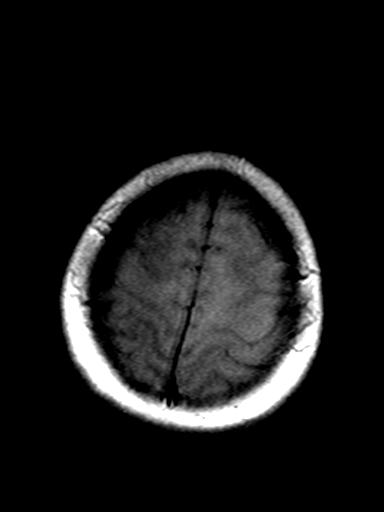

发热、头痛伴精神异常1周

较对称性脑白质异常信号,深部白质t2明显低信号(铁质沉积过多?)

考虑脑白质病变,请结合临床病史及实验室检查进一步分析。